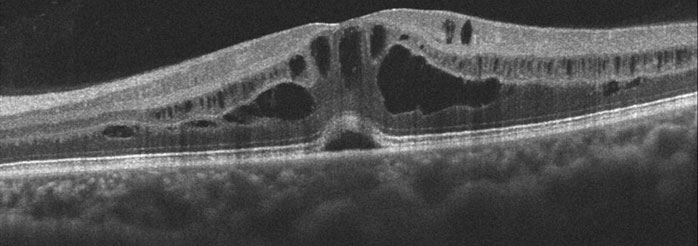

Cystoid Macular Edema (CME)

Cystoid macular edema (CME) is a swelling of the central macula, the portion of the retina responsible for our straight-ahead vision. It causes painless central vision blurriness or distortion. There are numerous causes, including eye inflammation (iritis, uveitis and pars planitis), diabetes, hypertensive retinopathy, retinal vein occlusion, and following cataract surgery.